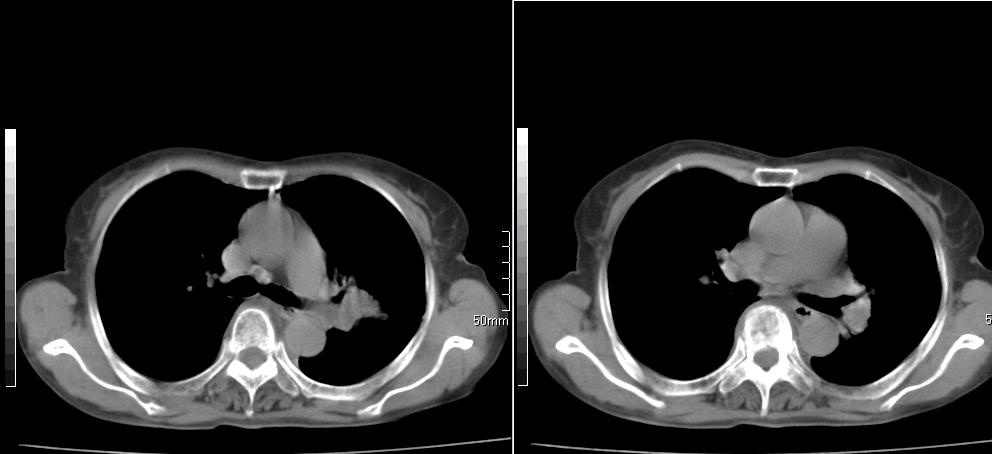

标题: CT26857:女,60岁,胃部不适前来就诊,不咳嗽,乏力,胸椎 [打印本页]

标题: CT26857:女,60岁,胃部不适前来就诊,不咳嗽,乏力,胸椎

1、胸椎有骨质破坏伴周软组织,考虑胸椎转移。2、考虑左肺上叶尖后段支气管开口区周围型肺癌可能。

1、胸椎有骨质破坏伴周软组织,考虑胸椎转移。2、考虑左肺中央型肺癌可能。

支持中央型肺癌,胸椎转移。

1)考虑左肺中央型肺癌。2)胸椎转移瘤不排除;建议行mri检查。